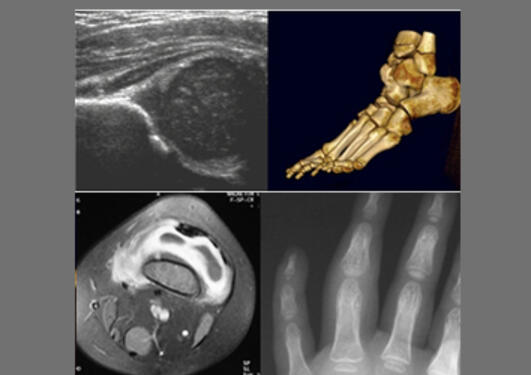

Ved K1 har vi grunnlaget for mye medisinsk forskning, nemlig gode pasientmaterialer. Samarbeid i klinisk medisin skal være fleksibelt og opportunistisk. Man knytter kontakter lokalt, nasjonalt og internasjonalt, søker aktivt etter muligheter og utnytter samarbeid. Samtidig sikrer noen stabile konstellasjoner over tid forskning med tyngde og gjennomslagskraft. De beste forskningsgruppene kombinerer stabilitet og fleksibilitet.

K1 er organisert i 11 seksjoner. Forskningsgruppene går på kryss og tvers av både seksjoner, institutt og institusjoner. Godt definerte forskningsgrupper fremmer forskning, styrker søknadskraft og rekrutteringsevne, og slike grupper medfører at alle deltagere skjerper seg ytterligere.